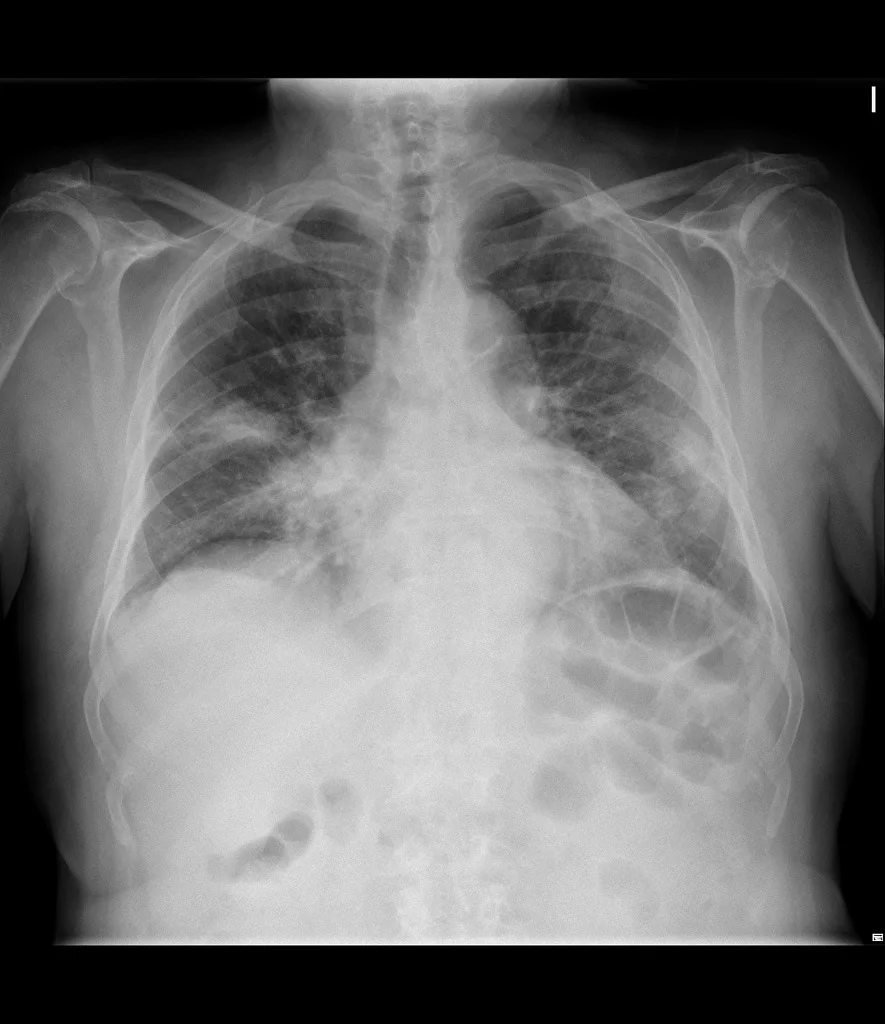

করোনা সংক্রামিত কিনা জানা যাবে এক্স রে রিপোর্টেই! নয়া পদ্ধতি আবিষ্কার মুসলিম বিজ্ঞানীর